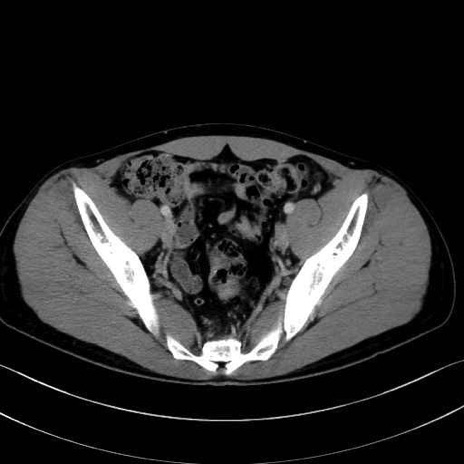

大腿筋膜張筋 (Tensor fasciae latae)